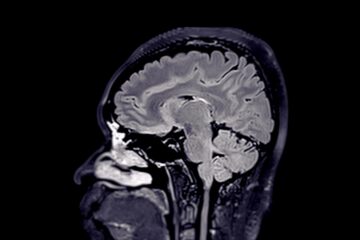

Gilus miegas (NREM 3 etapas), į kurį čia sutelkiame dėmesį, dar vadinamas lėto bangų miegu dėl būdingų lėtų delta smegenų bangų. Paprastai daugiau laiko praleidžiama šiame atstatomajame miego etape ankstyvą naktį.

Gilaus miego metu jūsų širdies ir kvėpavimo dažniai yra lėti, o raumenys atsipalaidavę, leidžiant jums pasinaudoti atstatomuoju miegu, kuris būtinas bendrai sveikatai. Dėl šios gilios atsipalaidavimo būsenos sunku pažadinti žmogų gilaus miego metu.

Tačiau norint gauti tikslius duomenis apie jūsų miegą, reikia atlikti medicininį miego tyrimą. Šie tyrimai stebi smegenų bangas, kad analizuotų jūsų miegą visą naktį.